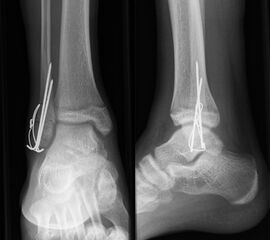

Behandlungsziel ist die exakte Rekonstruktion der Gelenkfläche sowie die Minimierung des Risikos einer späteren Wachstumsstörung. Dislozierte Frakturen werden offen reponiert, die Osteosynthese erfolgt mit einer Kleinfragmentschraube. Finden sich viele kleine Fragmente kann eine K-Draht Osteosynthese durchgeführt werden. Wird der Innenknöchel operiert, kann bei gleichzeitiger hochgradiger lateraler Instabilität eine Rekonstruktion des lateralen Bandapparats durchgeführt werden. Fibula Frakturen stellen sich meist spontan ein, sodass hier keine zusätzliche Osteosynthese notwendig ist.

Nach der Osteosynthese wird die Fraktur für ca. vier Wochen in einem Unterschenkelgips ruhiggestellt. Bei Schmerzfreiheit der Frakturzone erfolgt anschließend eine schmerzadaptierte Belastungssteigerung über weitere zwei Wochen. Sobald unter Alltagsbedingungen Beschwerdefreiheit besteht kann die sportliche Belastung langsam gesteigert werden. Kirschnerdrähte werden 6-8 Wochen postoperativ, Schrauben nach zwölf Wochen entfernt. Es empfiehlt sich klinische und radiologische Kontrollen im Abstand von 6 Monaten bis zum Wachstumsabschluss durchzuführen, um ein mögliches Fehlwachstum frühzeitig zu erkennen.